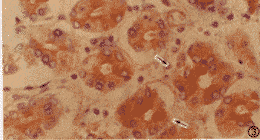

HCV NS3、NS5和CP10抗原阳性颗粒呈棕黄色、密集,定于肝外组织细胞浆内,呈均质型,包函体型和膜下型,未见核型。肾脏的肾小管上皮细胞、间质细胞(图1)和肾小球细胞内存在HCV抗原,以前两种细胞内常见,后者偶可见到。肾皮质内表达阳性细胞数量较髓质多。胰腺的腺泡细胞和腺导管上皮细胞(图2),肠道的肠腺上皮细胞(图3)和心脏的心肌细胞(图4)内也可检出HCV抗原。

图2 HCV NS5阳性表达位于胰腺导管上皮细胞浆内(↑指);数个以上阳性细胞聚集;S-P法×400

肝外脏器内抗原表达阳性细胞数量较相应肝组织(阳性肝细胞数量<1%)有较明显偏少;不同脏器间亦有一定差异,如心脏内较肠道、肾脏和胰腺偏少等。阳性细胞常以单个或数个聚集呈小灶状散在于组织内,多见于心脏和肾脏;也可数个以上聚集成不规则小片状,多见于胰腺和肠道。抗原表达阳性细胞的形态和大小与表达阴性细胞类似,未见特殊病变。